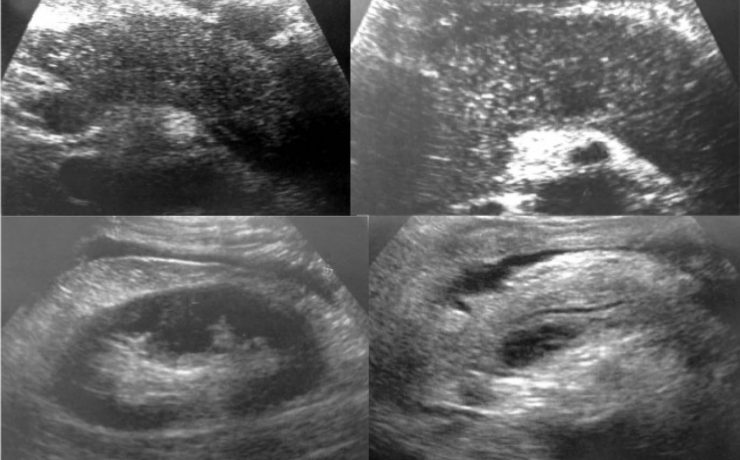

El hígado graso no alcohólico afecta a un tercio de la población en general, que puede desencadenar, cirrosis hasta un hepatocarcinoma. Estudios previos indican que La regeneración hepática en el hígado graso no alcohólica se ve involucrado un mecanismo de acumulo graso en el hepatocito